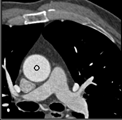

Samples for ascending aorta detection (black circle):

Cluster of candidate points in the ascending aorta.